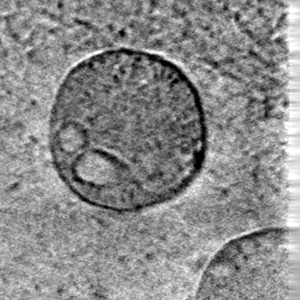

Scientists leading our project Science Scribbler need you to help annotate images of cells. This will help advance their research to understand illnesses such as Hutchinson’s disease.

Contribute to Science Scribbler here: www.zooniverse.org/projects/msbrhonclif/science-scribbler